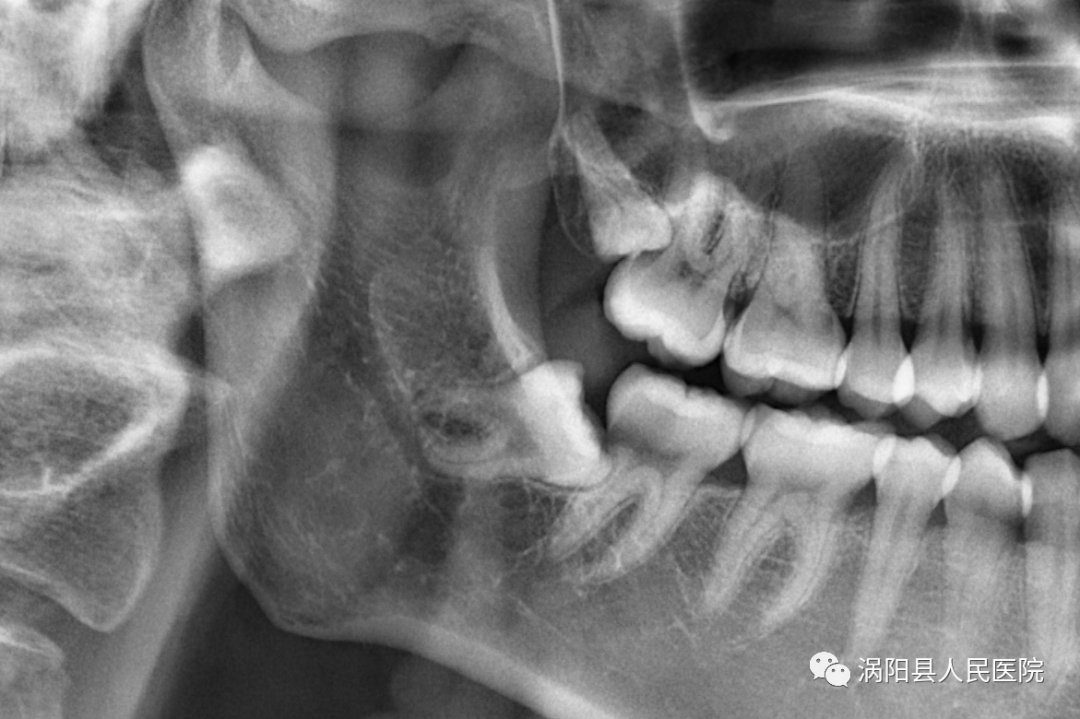

术前影像资料可见上颌第三磨牙完全埋伏、阻生且牙根紧贴上颌窦,拔除困难、术中稍有不慎,埋伏的阻生牙易进入上颌窦内,造成上颌窦穿通。